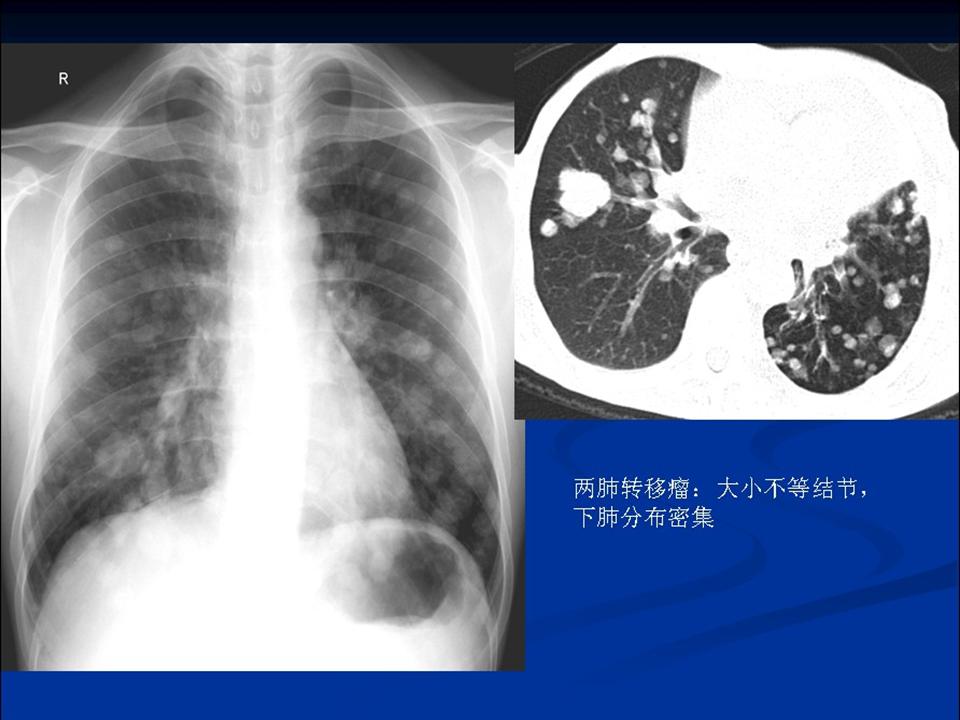

肺转移瘤与韦格肉芽肿影像鉴别